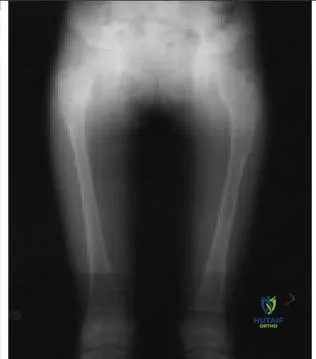

Question 10

An 8-year-old girl fractures her right femur when starting a sprint. Based on her radiograph (Slide), which of the following is the most likely diagnosis:

Explanation

This patient has signs of a pre-existing fibrous dysplasia lesion, including a central expansion of the subtrochanteric region with a ground-glass (not lucent) appearance. She was diagnosed with fibrous dysplasia.